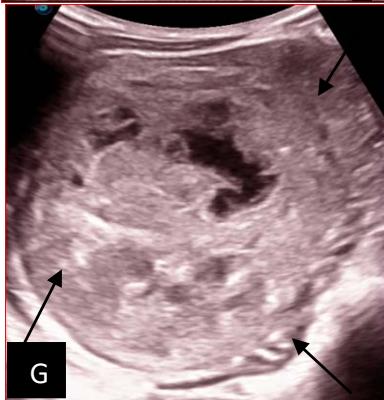

Figure 5: Abdominopelvic ultrasound control after 6 courses of chemotherapy in the same 3 year old patient with a ruptured left renal nephroblastoma; Images A, F, G, and H: show regression of the solid, endo and exo renal, left nephroblastoma mass treated with 6 courses of chemotherapy (current volume 430 ml vs) Images: B, C, and: show persistence of thrombotic permeation pan vena cava and ipsilateral renal. Image E: shows a volumetric regression of the intra-lesional hematic collection, at the tumor rupture estimated at 34.49 ml VS, Image I: represents the right kidney in B mode which is of normal echoculture. Source: Dr. Frederick Tshibasu Tshienda database.